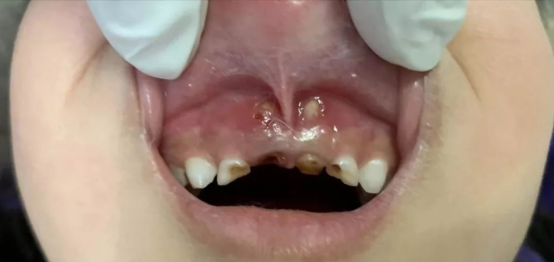

当孩子乳牙有了龋齿,如果家长不及时为孩子治疗“生病”的乳牙,等到孩子自己喊疼了,吃东西不舒服了,或者牙龈长脓包了,这时多数虫牙已经发展到了牙髓炎或者根尖炎的阶段,这种情况下的治疗就需去除乳牙的牙髓,不仅增加了孩子痛苦,还可能影响恒牙的萌出和生长。如果乳牙龋齿早期发现,只需要经过简单的充填,就会达到很好的临床治疗效果。所以建议粑粑麻麻们如果发现孩子患有乳牙龋齿,要及早带其到医院进行检查和治疗,不要延误最好的治疗时机,以免给孩子带来更多的痛苦。

乳牙龋齿不及时处理的危害:

龋齿造成的破损牙冠易损伤局部唇、颊、舌的黏膜,形成创伤性溃疡。